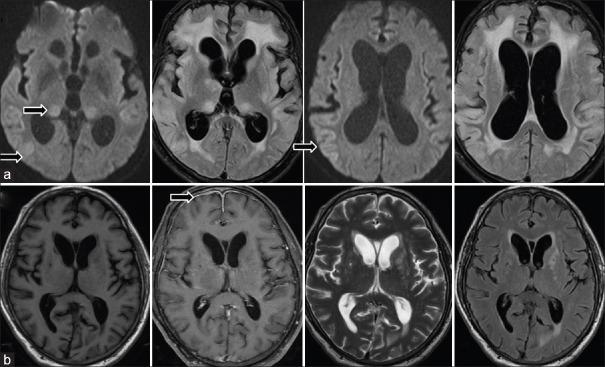

Neurosyphilis (NS) is a rarely encountered scenario today. Manifestations are heterogeneous, and their characteristics have changed in the antibiotic era. A differential diagnosis of NS is not commonly thought of even with relevant clinical-radiological features, as it mimics many common neurological syndromes.

CONCLUSIONS

NS dementia and behavior changes are mistaken for degenerative, vascular, nutritional causes, autoimmune encephalitis or prion disease. Meningitis has similarities with infective (tubercular), granulomatous (sarcoidosis, Wegener's), collagen vascular disease and neoplastic meningitis, and myelitis simulates demyelination or nutritional myelopathy (B deficiency). Rarely, NS can also present with cerebellar ataxia. Contemplate NS as one of the rare causes for such syndromes, and its early treatment produces good outcomes.

神经梅毒(NS)如今已较为罕见。其表现具有异质性,在抗生素时代其特征也已发生变化。即使具有相关临床 - 放射学特征,NS的鉴别诊断也不常被考虑,因为它可模仿许多常见的神经综合征。

结论

NS所致痴呆和行为改变常被误诊为退行性、血管性、营养性病因、自身免疫性脑炎或朊病毒病。脑膜炎与感染性(结核性)、肉芽肿性(结节病、韦格纳肉芽肿)、胶原血管病及肿瘤性脑膜炎有相似之处,脊髓炎可模拟脱髓鞘或营养性脊髓病(维生素B缺乏)。NS也可罕见地表现为小脑共济失调。应将NS视为这些综合征的罕见病因之一,早期治疗可产生良好预后。